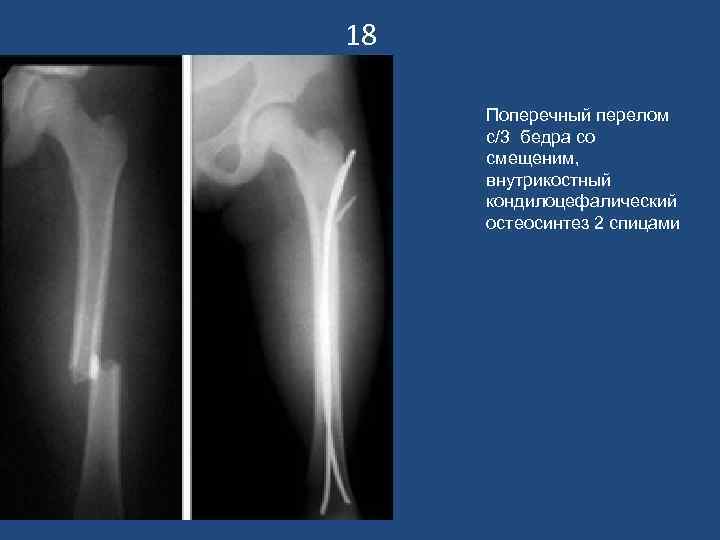

18 Поперечный перелом с/3 бедра со смещеним, внутрикостный кондилоцефалический остеосинтез 2 спицами